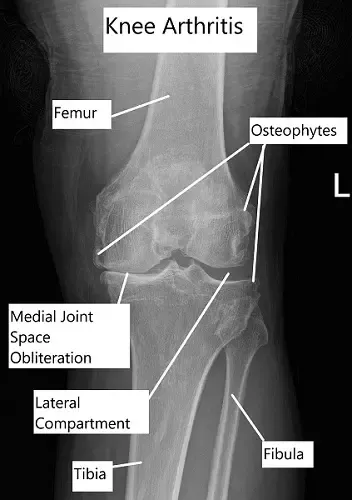

With degenerative changes in the joint, the articular cartilage erodes causing the bones to grind against each other. The constant grinding causes pain and crepitus. OA involves all the tissues forming a synovial joint including articular cartilage, muscles, bones, joints capsule and ligaments.

- Intermediate Stage: The new blood vessels invade the bone underlying the articular cartilage called subchondral bone and increase its size. The cartilage degradation continues till it breaks and either dissolves in the joint or come to lie as “loose bodies”. The bone thickening is especially more prominent towards the sides of the joint forming bone spurs.

- Late Stage: Articular cartilage is lost with a thickened and swollen underlying bone. Cysts or cavities develop in the bone and the synovial tissue increases in size due to swelling. An increased amount of pressure exists in the joints.

- Imaging: X-ray is usually the first investigation done to check for joint space and thickening of the bones. For a detailed evaluation, a CT scan can be done but usually, an MRI is the most helpful investigation. It details all the structures inside the joint.